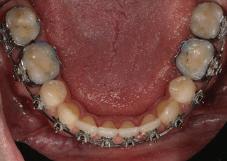

Пациентът постъпи в моята клини ка с наличие на темпоромандибуларен дисфункционален болков синдром, едно странно изместен диск с редукция в дяс ната става, клас II, подклас 2, тесни гор на и долна челюст със струпване, дъл бок овърбайт

орални снимки и снимки на позата, пал пация на мускулите, брукс-чекър, оклу зограми, кондилография, рентгеногра фии, СВСТ и ядрено-магнитен резонанс на темпоромандибуларните стави). Преди началото на ортодонтското лечение всички стари възстановява ния бяха свалени и бяха заменени с дъл госрочни временни от хибридна керами ка. На девитализираните зъби бе прове дено ендодонтско релечение. Индивиду ализиран оклузален сплинт бе направен с цел да се постигне контролирано репо зициониране на долната челюст, като носенето му продължи три месеца до възстановяване на правилната позиция на ставния диск и затихване на орофаци алната болка и дискомфорт в ставата. Брекетите в горната челюст бяха за лепени, за да започне подреждането и нивелирането на зъбите, докато паци ентът все още носеше сплинта. След края на терапията със сплинта бе на правена кондилография, за да се потвър ди триизмерната позиция на долната челюст. След залепване на брекетите в долна

тация на долната челюст. Дъга GUMMETAL с tip-back извивки бе поставена в долната челюст за ниве лиране кривата на Шпее. Случаят бе финализиран с 19x25 SS дъги в горната и долната зъбна дъга за координиране. Преди да се изготви финалният восъ чен моделаж, естетичните и лицеви те характеристики бяха анализирани с помощта на дигитален дизайн на ус мивката, за да се създаде мок-ъп, чии то форма и размери да бъдат одобрени от пациента. Бе оценена фонетиката и бяха заснети лицеви снимки и видеа. Зъ бите бяха изпилени, като препарация та бе изцяло водена от функционалния восъчен моделаж, прехвърлен в устата на пациента. След препарацията восъч ният моделаж бе напаснат и насложен върху препарационния модел и бе фрезо ван от e-max multi bl 1. Циментирането на финалните конструкции бе направе но при изолация с кофердам, следвайки адхезивния протокол. След циментирането бе направено проследяване на оклузията чрез снема не на отпечатъци, монтиране на моде лите в артикулатор в окончателната интеркуспидация и внимателно прове ряване за наличие на блокажи при воде ни движения.

та челюст 4 минивинта (TADs) бяха по ставени в максилата – 2 в небцето и 2 интрарадикуларно във фронта, с цел да се извърши интрузия на цялата зъбна дъга, да се коригира гингивалната усмивка и да се позволи провеждането на обратна на часовниковата стрелка авторо